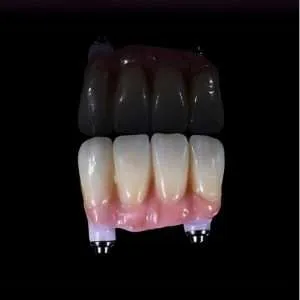

Si buscas rehabilitar tu boca completa, los precios por arcada (como la técnica All-on-4) pueden ir de $2.500.000 a más de $5.000.000, dependiendo si eliges materiales premium como el zirconio.

| Arcada Completa (All-on-4, All on X, híbrida, ad-modum, prótocolo, branemark) | $2.500.000 – $4.500.000 | Valor por arcada completa. Ideal para implante dental completo precio. |

| Arcada Completa en Zirconio | $4.200.000 – $6.000.000 | Máxima estética y durabilidad por arcada. |

Calidad de la Corona: Trabajamos con coronas digitales de material CAD/CAM fresado (Zirconio u otro), lo que garantiza un ajuste perfecto y una estética natural superior a la metal-cerámica antigua.

Hacen implantes de zirconio

Actualmente trabajo implantes de titanio con corona de zirconio.